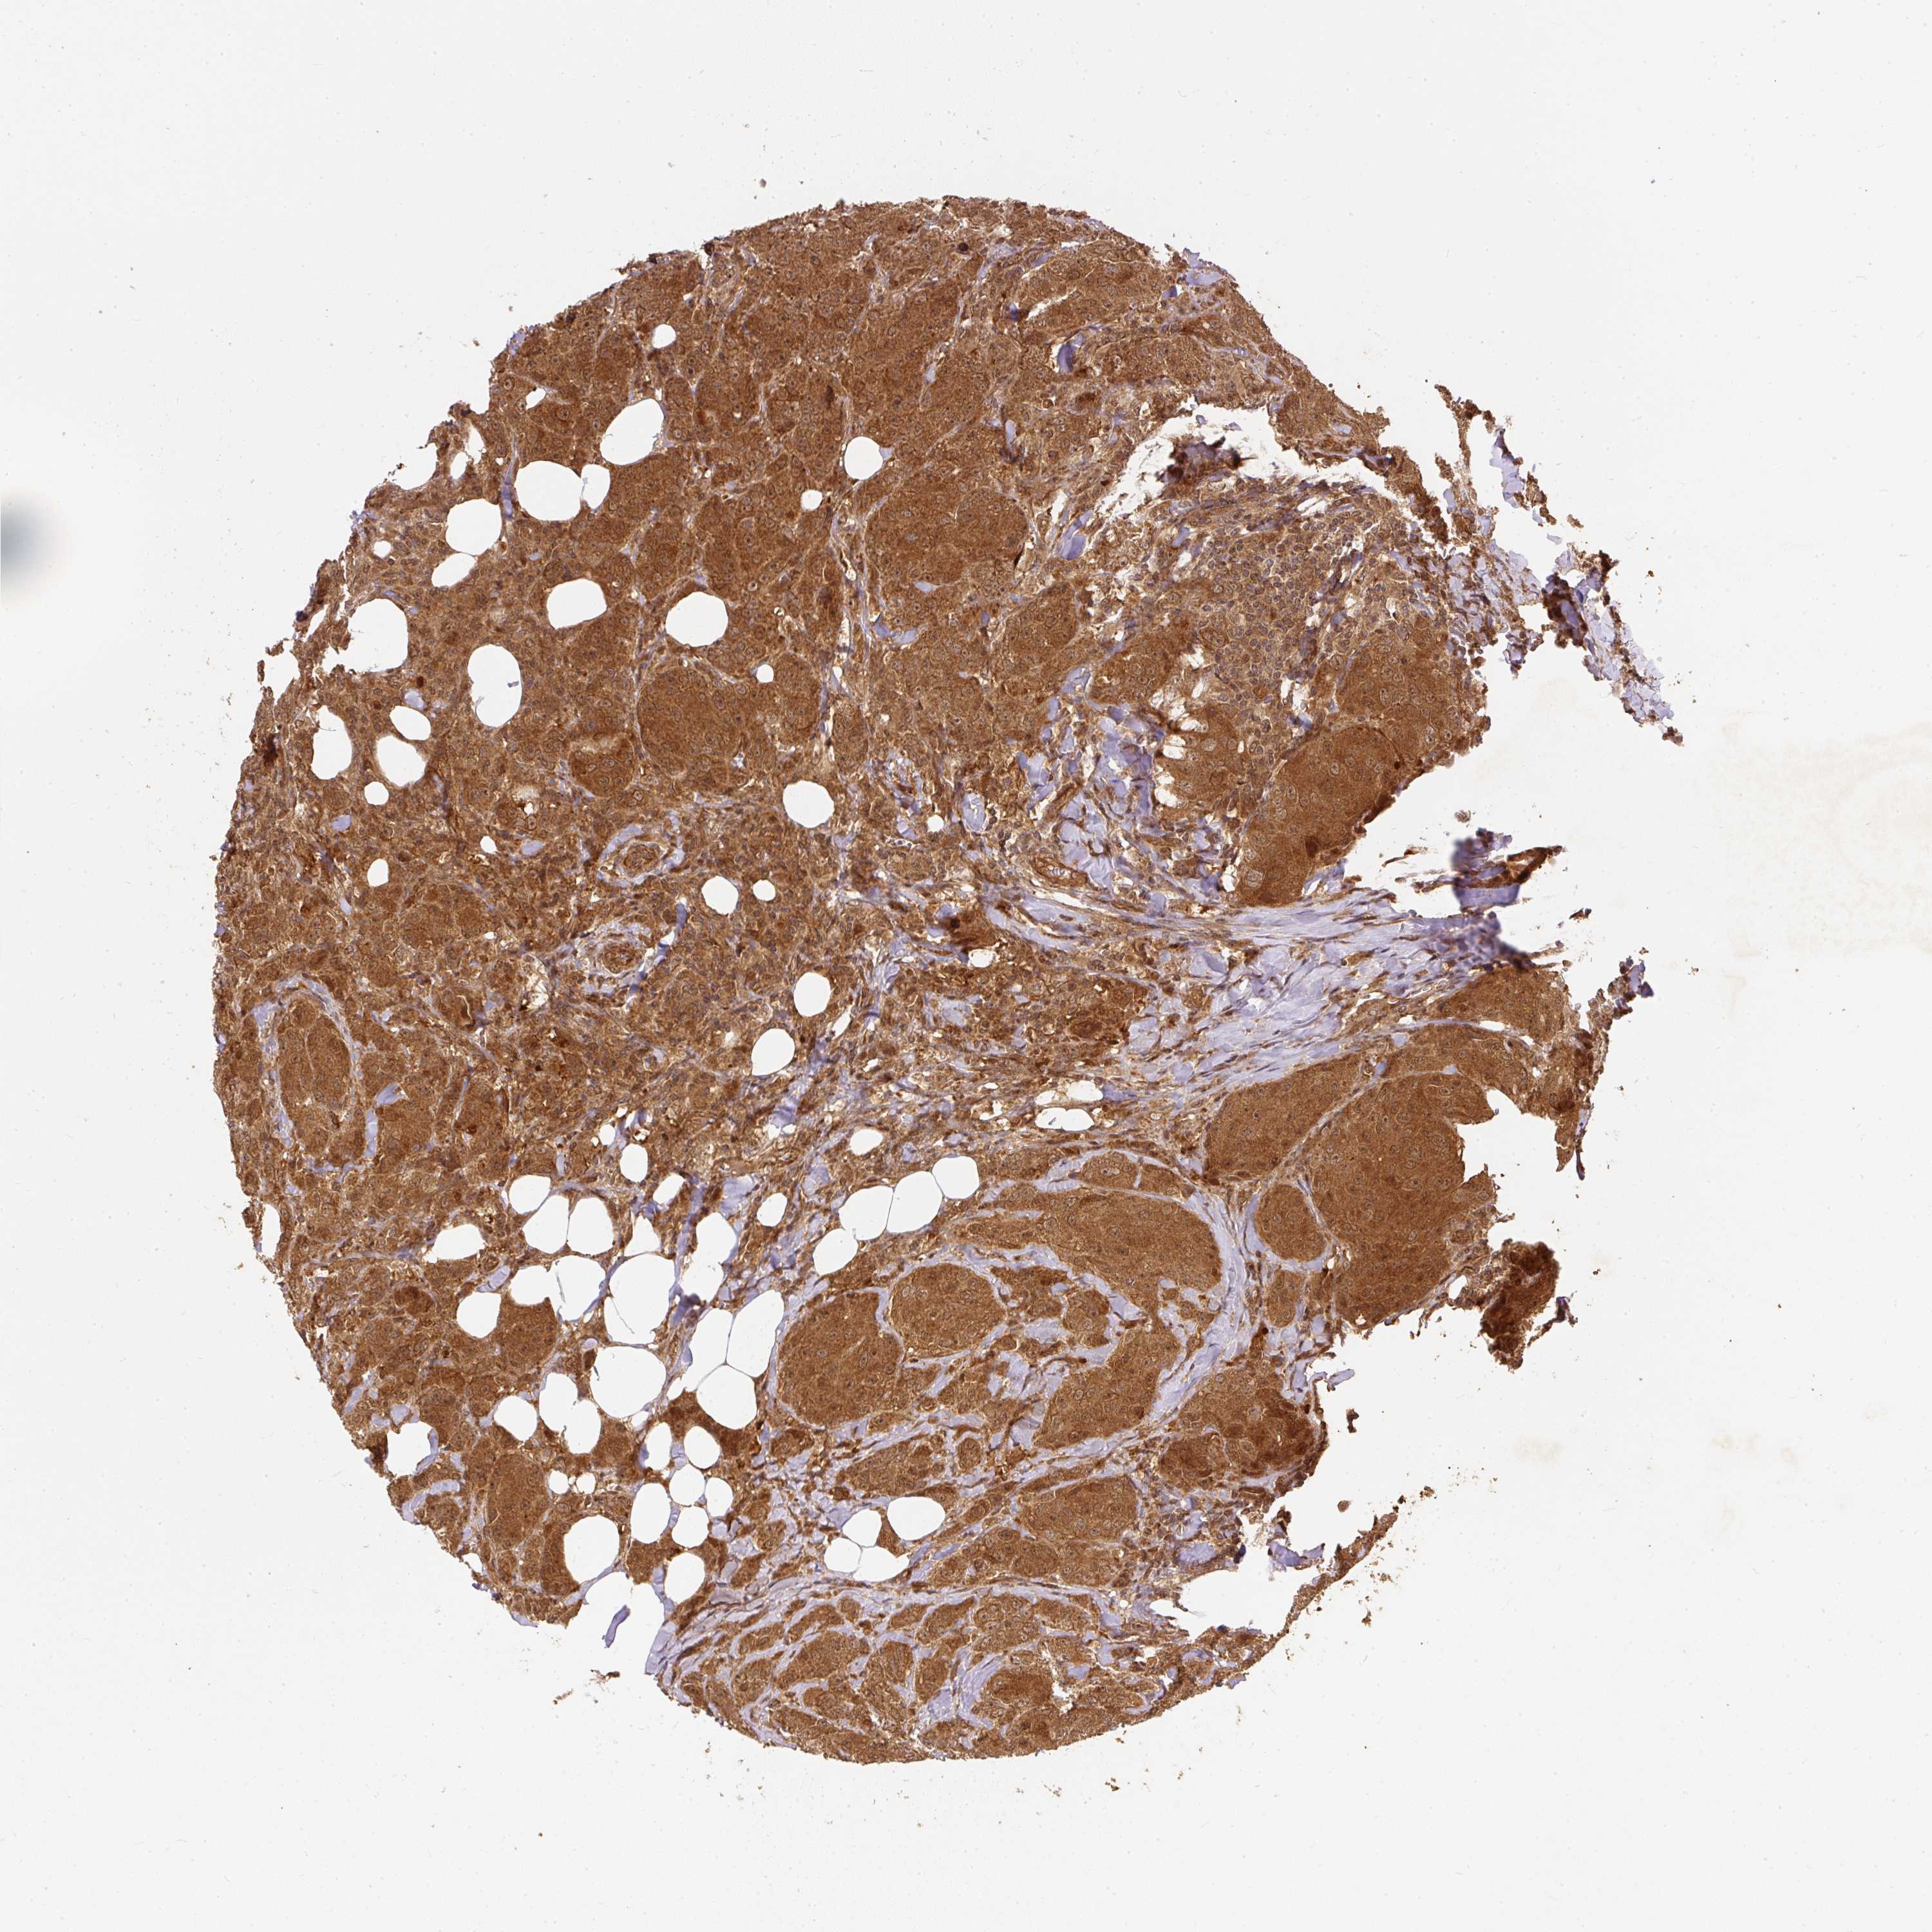

CANCER BREAST CANCER Show tissue menu

BRCA TCGA BRCA VALIDATION PROTEIN EXPRESSION